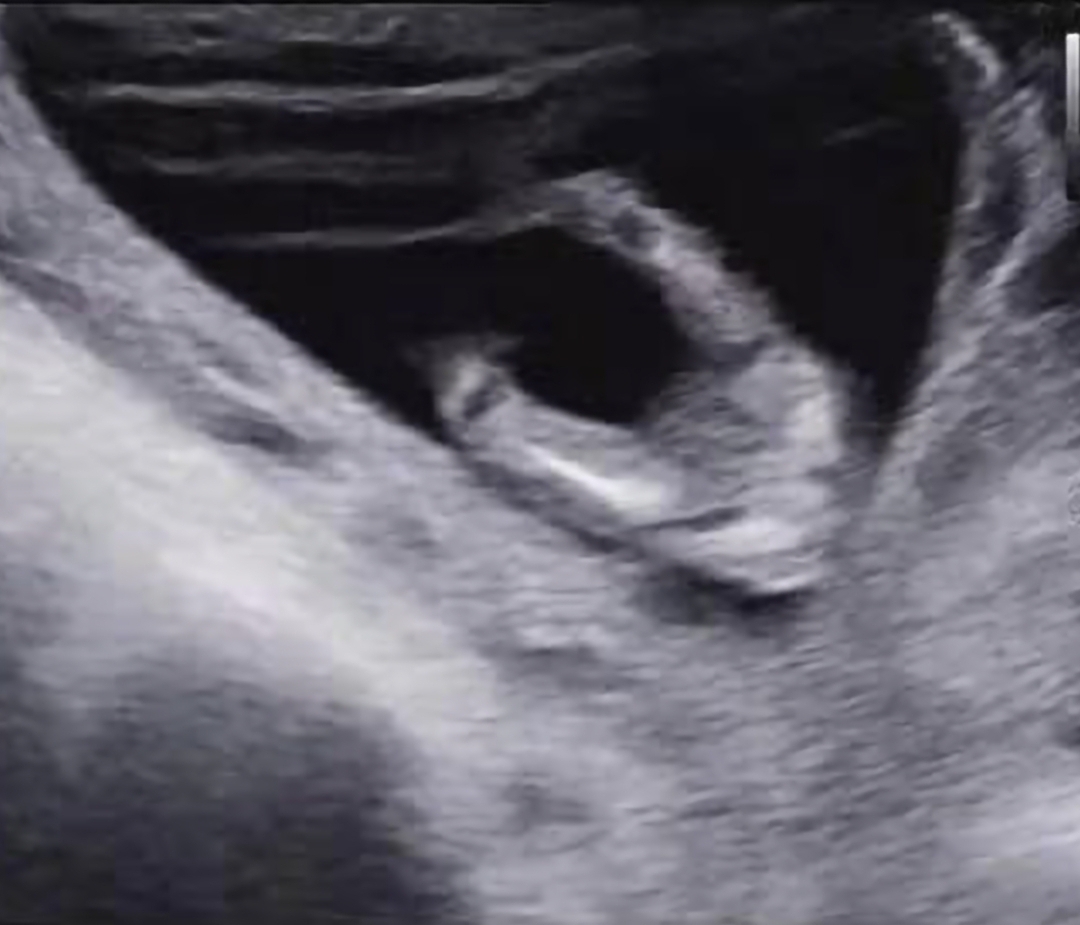

여자아이겠죠...? 13주3일에 찍은건데 성별 바뀔가능성이 있을까요?

13주면 바뀔가능성도 있어요

저도 딸인뎅, 촘파 사진 비슷해용! 아들이면 뭐라도 튀어나와있대요!

여아같아요~ 😉

딸같네용